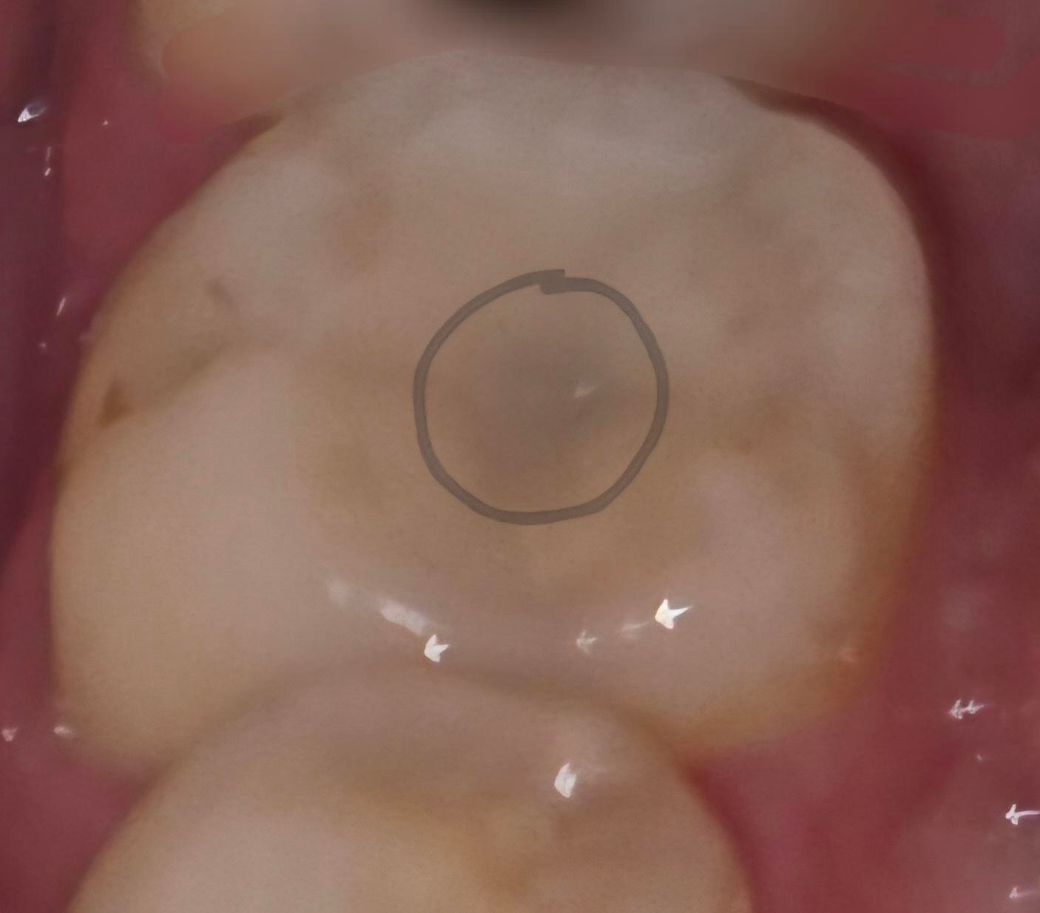

세라믹 새로 붙이고나서 어금니를 카메라로 찍었었는데

충치가 있었다면 사진상 검게 나타나는게 있어야하는데

사진상으로는 그냥 깨끗한 치아사진으로 찍혀있으니

문제없는거라고 해서 일단 집에왔어요

집에왔는데도 먼가 께름찍해서 여기에 다시 여쭤봅니다

세라믹 떨어진 자리에 오염물 다 긁어냈고

치과용 엑스레이?로 찍은 사진에 충치로 보이는것도 없는데

왜 육안으로 볼때 어금니 가운데 중앙쪽이 회색으로 보일까요? 예전에 다른치아 세라믹 했을때 이런적 한번도 없었는데ㅠ치과선생님들 이유를 알려주세요 ㅠ

• 2번 째 사진

일반적으로 인레이 하방으로 비쳐보이는 회색빛은 이차충치를 의미하나 세라믹을 최근에 새로 한 것이라면 분명 세라믹을 위한 치아 모양 만들면서 충치는 다 제거했을 겁니다.

다음의 가능성이 있습니다

1. 인레이 하방 기저재 색상

2. 인레이가 얇아 접착제 색상이 비치는 경우

뒤에 치아도 아말감으로 때워져있는 걸로 봐서 해당 치아도 기존에 아말감착색이 남아 어둡게 비치는걸로 생각됩니다. 아말감 착색까지도 제거하게 되면 불필요한 신경치료가능성도 있기 때문에 제거를 안한듯이 보여집니다. 아말감 착색이 맞다면 나중에 충치로 되거나 하는 걱정은 안하셔도 좋을거 같습니다.

기존에 아말감을 햇던 자리에 아말감 착색이 잇는 부분이 비춰보이는거 같습니다. 큰 문제가 잇는건 아닙니다.